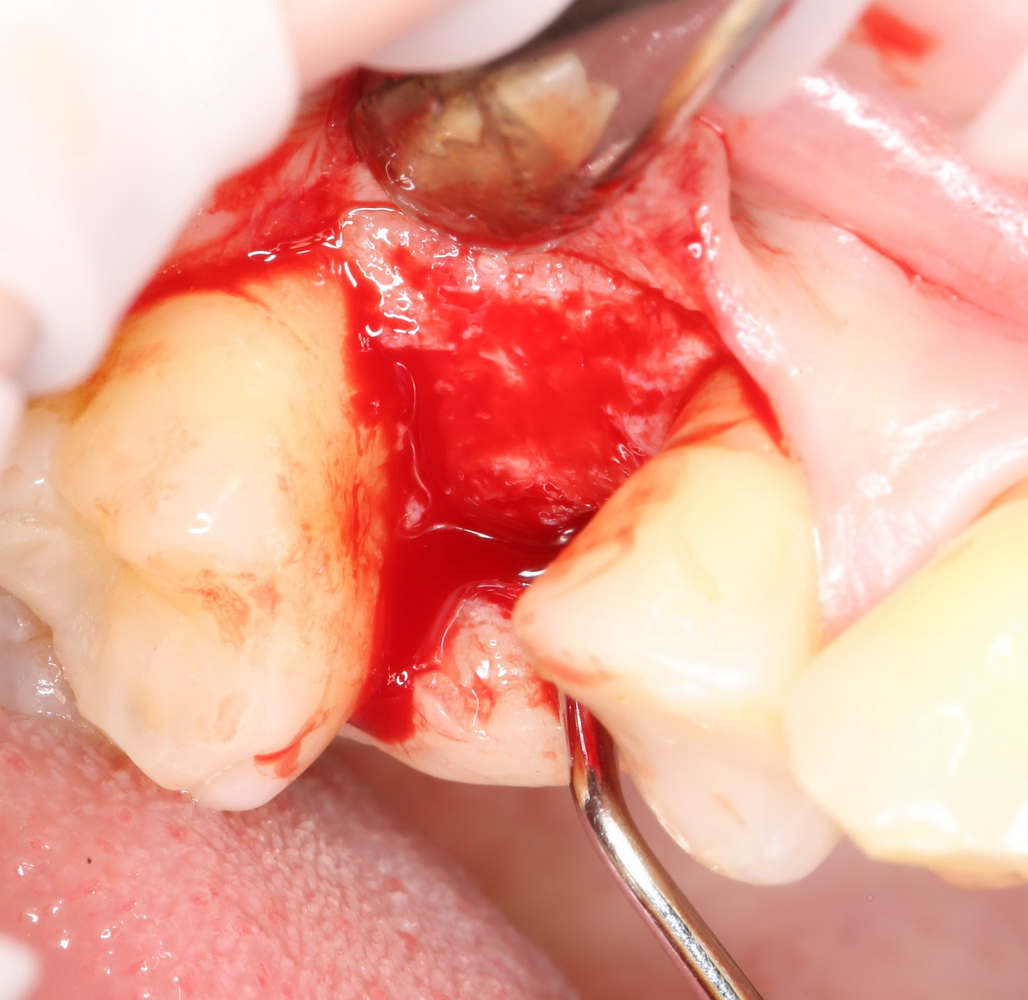

Ну и, зуб проще удалить, если ты видишь, что от него осталось. Что мы и делаем:

Вместе с зубом удаляется прикорневая гранулема. После того, как из лунки удалены все патологически измененные ткани, можно подумать о том, как сохранить объемы альвеолярного гребня в этом участке для будущей имплантации.